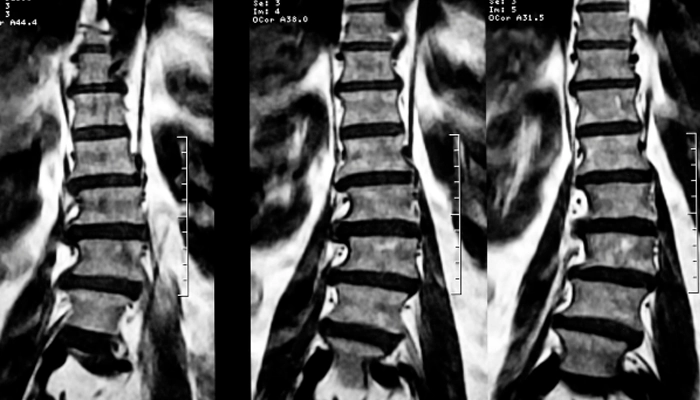

4.3. Chụp MRI (Cộng hưởng từ)

Là phương pháp chẩn đoán chính xác nhất, cho phép thấy rõ tình trạng tủy sống, rễ thần kinh và mô mềm, xác định vị trí hẹp cụ thể.

Hình ảnh chụp Xquang hẹp ống sống